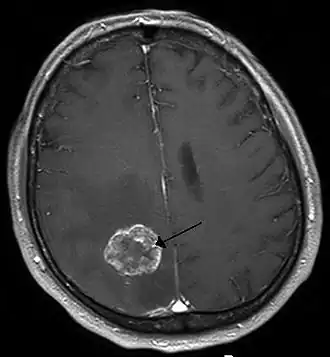

Por un proceso de epilepsia se entiende por el contrario una enfermedad-epilepsia, consecuencia de una enfermedad neurológica progresiva (proceso en continuación, no concluido). El ejemplo más importante y común en un proceso de epilepsia es el tumor cerebral, aunque también pueden conducir a una epilepsia los trastornos vasculares o enfermedades metabólicas. Puede ser una manifestación de la enfermedad de Wernicke.

La epilepsia así como las crisis epilépticas pueden en la actualidad recibir un tratamiento con resultados aceptables. En la mayoría de los casos, las epilepsias de la infancia se curan en la pubertad.[32] Cuando la epilepsia se debe a una lesión claramente visible y esa lesión es eliminada quirúrgicamente, se reduce la intensidad y frecuencia o bien, en muchos casos, se cura la epilepsia.[33] Por lo tanto, al comienzo del tratamiento se examina al individuo, en busca de causas de la epilepsia que se puedan eliminar, por ejemplo, la operación de un tumor cerebral o la supresión o mitigación de un trastorno metabólico.

La neurocirugía está indicada cuando la epilepsia es resistente a los AEDs. La cirugía puede ser paliativa o curativa. La paliativa se realiza en los casos de epilepsias catastróficas. La valoración de realizar una cirugía resectiva, que pueda ser curativa, debe realizarse antes del planteamiento de realizar tratamientos paliativos como la estimulación del nervio vago. Esta valoración tiene dos fases: una no invasiva y una invasiva; la no invasiva consiste en realizar estudios clínicos que no necesitan de una intervención quirúrgica. Estos estudios son: EEG basal, un video monitoreo, una IRM de cerebro con características especiales, de acuerdo con el tipo de epilepsia que se esté investigando. Pueden sumarse estudios de S.P.E.C.T. o de P.E.T. Siempre incluye además una valoración neurosicológica.[39]

Los estudios de Fase 2, que necesitan de una cirugía son: la colocación de electrodos subdurales o la estimulación cortical transoperatoria. A esta fase se llega en los casos de difícil diagnóstico, o en los que no hay una lesión visible en las imágenes.